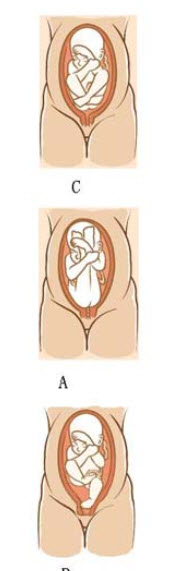

6ЎўГыҙКҪвКН

ЧЭІъКҪ(Longitudinal Lie)

98ЎўГыҙКҪвКН әбІъКҪ(Transverse Lie)

98ЎўГыҙКҪвКН әбІъКҪ(Transverse Lie)

112ЎўГыҙКҪвКН МҘІъКҪ(Fetal Lie)